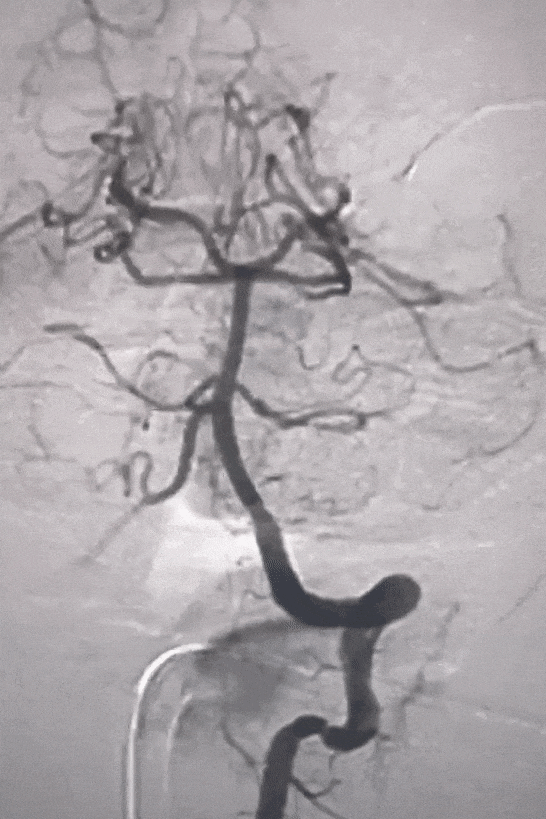

冒烟见基底动脉、双侧大脑后动脉显影较好。同轴系统缓慢跟进中间导管至V4段,支架展开后等待5分钟,缓慢整体回撤支架系统、同时负压抽吸中间导管。支架撤出体外见支架内血栓,造影见:基底动脉、双侧大脑后动脉、双侧小脑上动脉、双侧小脑后下动脉显影。

支架取出的血栓

取栓后造影

回撤6F 长鞘至左侧椎动脉V2段行3D造影,可见V3段夹层,远端血流正常,前向血流TICI分级3级。

术中完善Dyna-CT未见明显出血,导管内缓慢给予替罗非班5ml,同时静脉维持泵入替罗非班(5ml/h)。术中观察20分钟后造影见:左侧椎动脉V3段夹层较前有所改善,前向血流稳定、前向血流TICI分级3级。